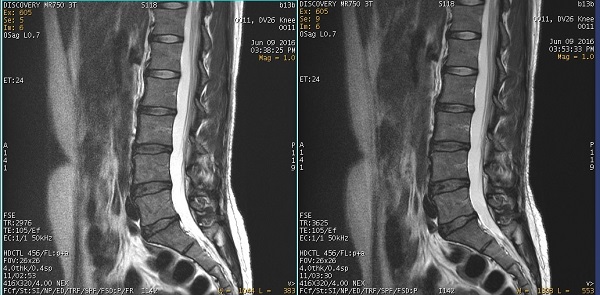

Figure 1. T2 image comparison: FRFSE on the left, FSE on the right

The Fast Recovery Imaging Option in is designed to enhance the intensity of fluids that have long T1 and T2 relaxation times, while using a shortened TR time. The shortened TR time makes the high resolution images practical. SNR is improved using FRFSE in comparison to FSE.